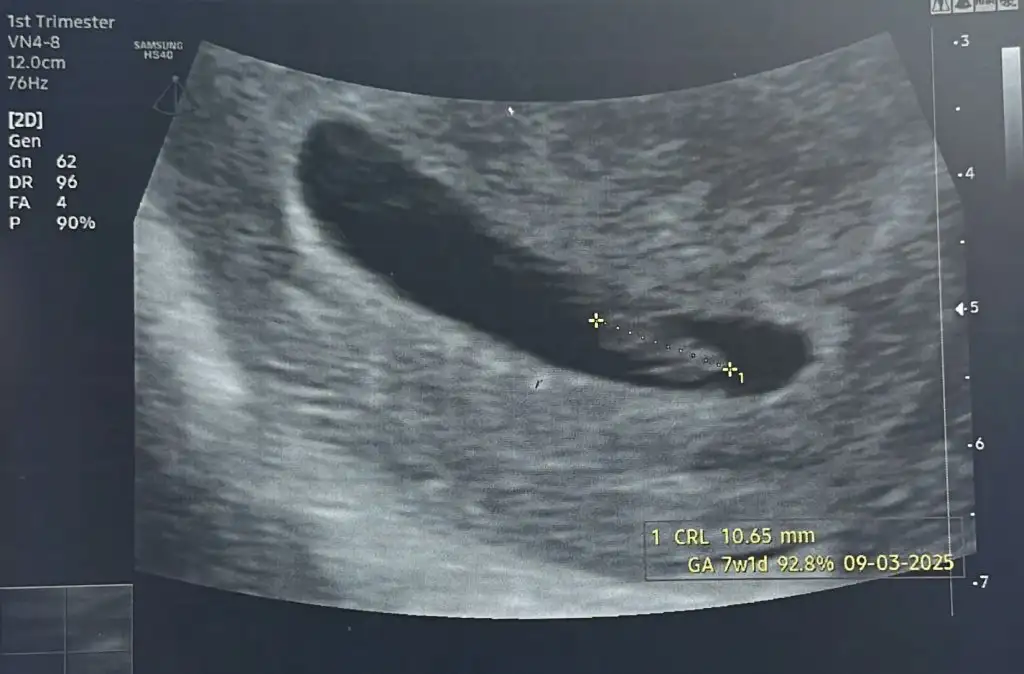

7 haftalık :)

• 1000035856.webp

1000035856.webp

21,9 KB · Görüntüleme: 44